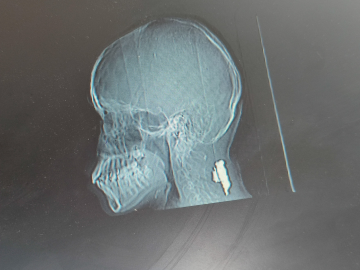

مخرج 'مهرجان أكون' الأردني يُصاب وأطفاله بقصف غزة .. ويناشد عبر 'سرايا' لاستكمال علاجه ومشروعه